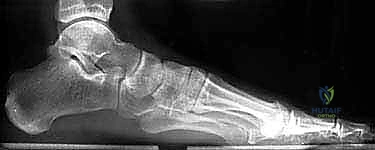

- الأشعة السينية (X-rays) متعددة الزوايا: لتقييم الانهيار العظمي وزوايا الكعب (مثل زاوية بوهلر وزاوية جيسان).

| ارتفاع الكعب (زاوية بوهلر) | طبيعي (20 إلى 40 درجة)، يدعم قوس القدم | منهار (زاوية مسطحة أو سلبية)، تسطح شديد للقدم |

- فقدان قوس القدم (Flatfoot Deformity): انهيار ارتفاع الكعب يؤدي إلى تسطح القدم، مما يغير من طريقة توزيع وزن الجسم ويسبب آلاماً تمتد إلى الركبة والورك وأسفل الظهر.